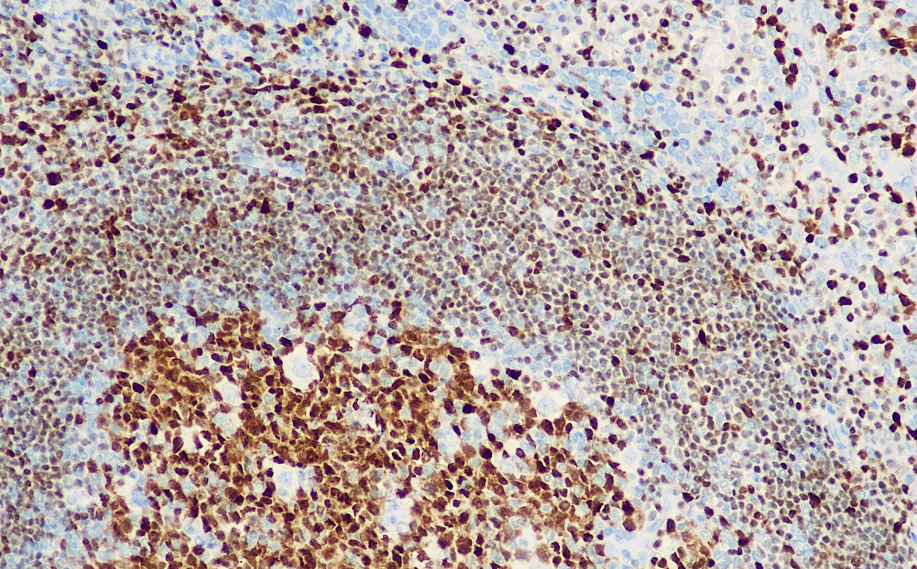

Positive control: tonsils

Oct-2 is a transcriptional activator required for the expression of B-cell immunoglobulin genes. It is usually expressed in the nucleus of B cells, including plasma cells (the expression of Bob.1 is stronger than that of Oct-2). This antibody is generally used in combination with Bob.1 and is mainly applied in the research of Hodgkin's lymphoma and large B-cell lymphoma. Some T-cell lymphomas can also be Oct-2 positive.

Oct-2 antibody reagents can specifically bind to Oct-2 molecular antigens. Immunohistochemical kits containing Oct-2 antibody reagents are suitable for the precise diagnosis of Hodgkin's lymphoma and large B-cell lymphoma.